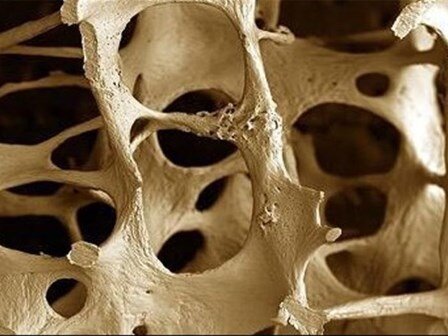

پوکی استخوان یکی از دلایل اصلی ناتوانی به خصوص در زنان مسن و یک اختلال ضعیف کننده استخوان است که اغلب منجر به شکستگی در لگن و ستون فقرات می شود که می تواند به شدت باعث آسیب و تحلیل شود.